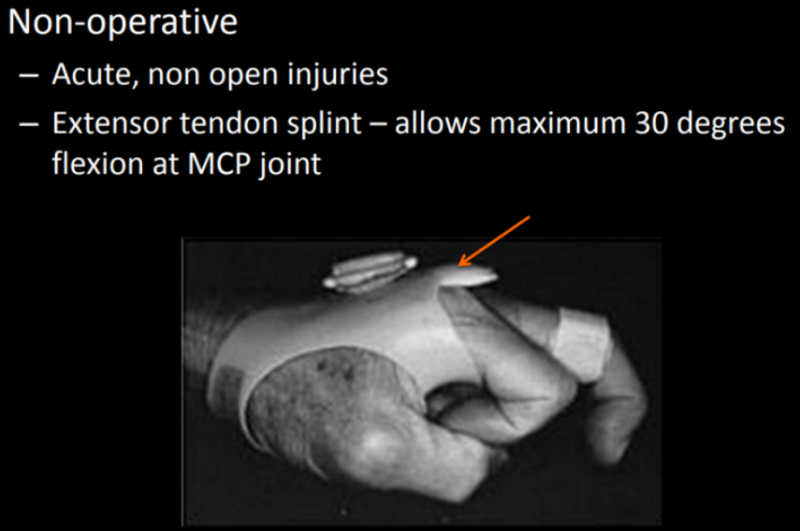

비수술 치료(수상 후 3~4주 이내)

다친 후 3~4주 이내에는 비수술적 치료가 우선입니다.

손가락을 펴게 한 후 고정시켜줍니다. 이때 손가락 굽힘을 30도까지만 제한해 주어야 합니다.